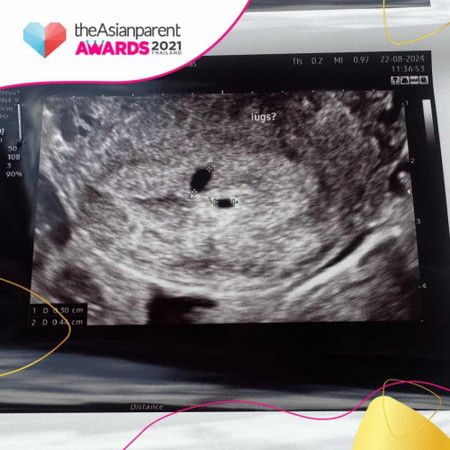

5w แบบนี้ครรภ์แฝดไหมคะ ซาวด์แล้วยังไม่เจอตัวน้อง หมอสันนิษฐานว่าอาจจะเป็นครรภ์แฝด หรืออีกถุงอาจจะเป็นถุงน้ำ หมอนักอีก 2 สัปดาห์ตรวจใหม่ กังวลมากเลยค่ะ 🥺